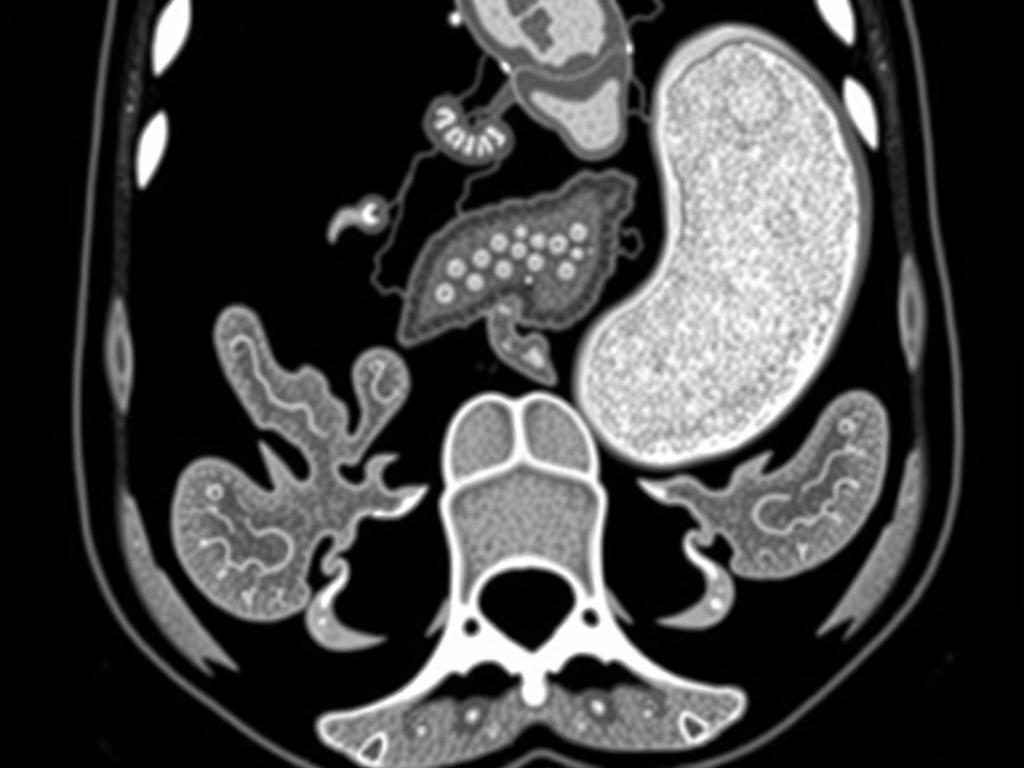

La tomografía computarizada ofrece imágenes transversales detalladas del abdomen que permiten ver el apéndice, su tamaño, la presencia de líquido, engrosamiento de la pared, y signos indirectos de inflamación o perforación. Antes de la adopción generalizada de la TC, el diagnóstico de apendicitis dependía en exceso de la exploración física, los síntomas y tablas de puntuación clínica. Eso llevaba a tasas de apendicectomías negativas (operar cuando el apéndice no está inflamado) y a retrasos diagnósticos peligrosos. Con la TC se redujo significativamente la incertidumbre, pero surgieron nuevos retos: interpretación dependiente del radiólogo, variabilidad entre observadores, y tiempos de espera en servicios saturados. Aquí es donde entra con fuerza la inteligencia artificial, no para sustituir la mirada experta, sino para estandarizar, acelerar y complementar la lectura de imágenes.

La TC es particularmente adecuada para el uso de IA porque genera datos estructurados en forma de volúmenes. Los algoritmos de aprendizaje profundo, y en especial las redes neuronales convolucionales (CNN), funcionan muy bien cuando tienen acceso a grandes cantidades de imágenes con etiquetas confiables. Cuando los modelos se entrenan con tomografías de pacientes confirmados con apendicitis y controles sin enfermedad, aprenden a detectar patrones sutiles que pueden pasar desapercibidos incluso para el ojo humano en situaciones de fatiga o carga laboral.

Las CNN son la columna vertebral de muchos avances en visión por computador. En el contexto de TC, las CNN 2D procesan cortes individuales, mientras que las CNN 3D procesan volúmenes completos, capturando relaciones espaciales en tres dimensiones. Para apendicitis, las CNN 3D tienden a ser más informativas porque preservan la anatomía volumétrica del apéndice y tejidos circundantes. Estas redes aprenden a distinguir tejidos inflamados, identificar colecciones y ver trayectos fistulosos sugerentes de perforación.

Dos tareas técnicas recurrentes son la segmentación (separar el apéndice y estructuras de interés del resto de la imagen) y la detección/classificación (decidir si hay apendicitis y su probabilidad). Para segmentación se usan U-Net y variantes 3D U-Net; para detección, arquitecturas basadas en CNN clásicas o modelos de clasificación más recientes. La segmentación también ayuda a medir el diámetro del apéndice y evaluar derrames periapendiculares de forma automatizada, ofreciendo métricas cuantitativas que refuerzan la interpretación clínica.